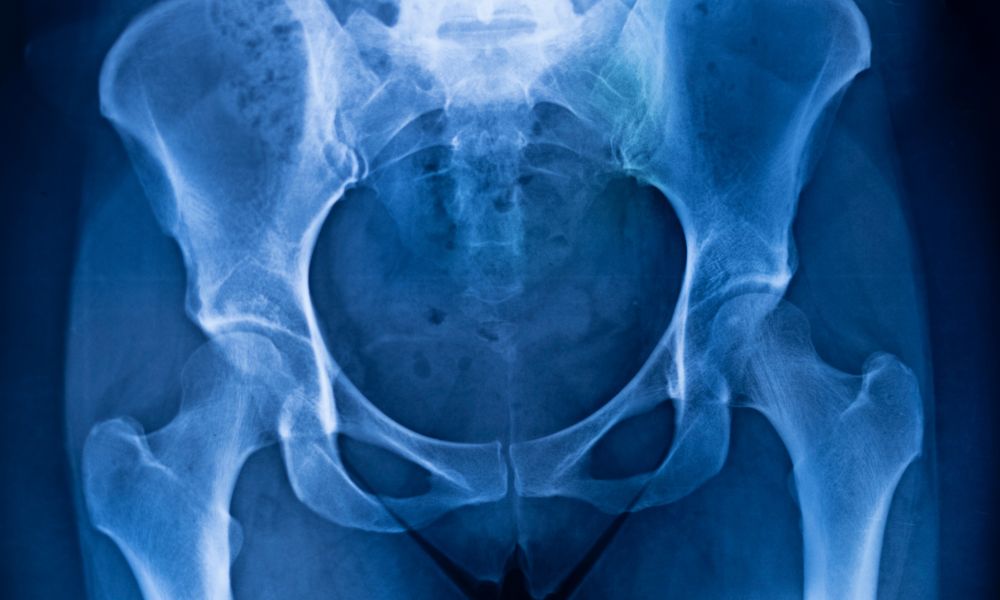

¿Sufres de dolor de cadera o necesitas un reemplazo?

El dolor de cadera puede afectar tu movilidad, calidad de vida y autonomía. Cuando los tratamientos conservadores ya no son efectivos, un reemplazo total de cadera puede ser la mejor solución para recuperar tu funcionalidad y eliminar el dolor.

¿Cuándo se necesita una cirugía de cadera?

Artrosis avanzada de cadera

Necrosis avascular de la cabeza femoral

Fracturas inestables del cuello femoral

Limitación funcional severa

Dolor persistente pese a fisioterapia y medicamentos

Tratamiento especializado en fracturas de pelvis y acetábulo

Las fracturas pélvicas requieren un manejo quirúrgico preciso y personalizado.

Con entrenamiento especializado en trauma ortopédico, abordo estas lesiones complejas con un enfoque integral, desde la estabilización inicial hasta la rehabilitación completa.